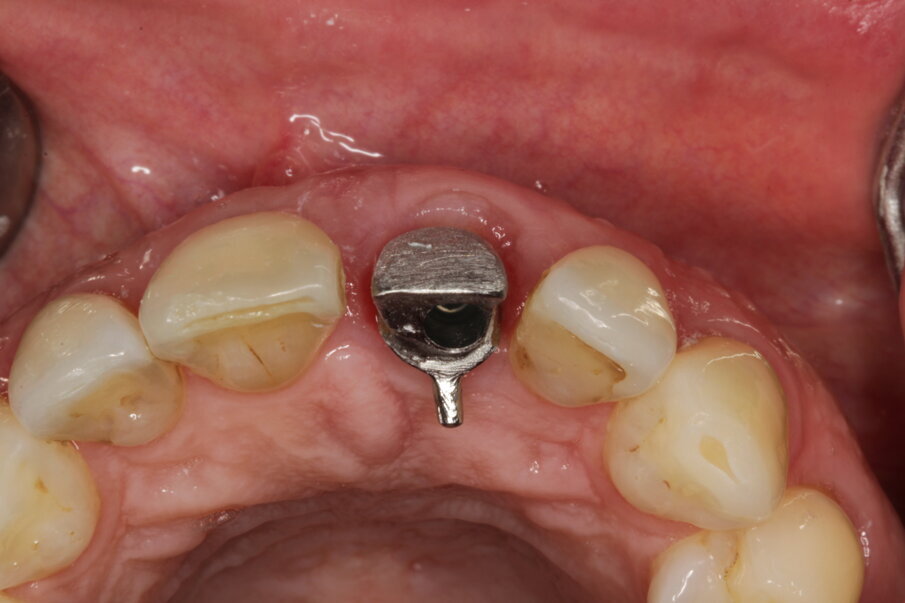

Eight days after surgery, the patient reported that healing was uneventful and the prosthodontist removed the stitches. It has become the author’s standard protocol to perform an intraoral scan for implant position in this same session (Figs. 24 & 25). The specific and unique PEEK healing abutment used has an internal circular channel and on one side, normally positioned on the buccal aspect, a vertical rectangular slot (Fig. 26). After removing the PTFE tape used to plug this area during surgery, a ScanPeg can be positioned inside the healing abutment. This allows for a unique scanning procedure without removing the healing abutment, thus avoiding disturbing healing tissue or dislocating recently placed biomaterials. The producer provides libraries for STL files of the five different anatomical shapes—wide incisor, narrow incisor, canine, premolar and molar—that determine the basic profile of the gingival tunnel during healing.

Temporary crown

The surgeon indicated that the healing abutment may be removed after four weeks. By then, the temporary screw-retained crown had already been fabricated by the technician, who had prepared a CAD/CAM-milled acrylic tooth glued on to a Neoss NeoLink abutment (Figs. 27–30). As a result of the decision to place the implant entirely in native bone, the angulation was such as to locate the screw access hole of the provisional on the buccal aspect. This can be easily camouflaged by a simple composite filling after plugging the channel with PTFE tape. The gingival profile copies in this first stage of loading the central incisor anatomy of the Neoss Esthetic Healing Abutment (Fig. 31).